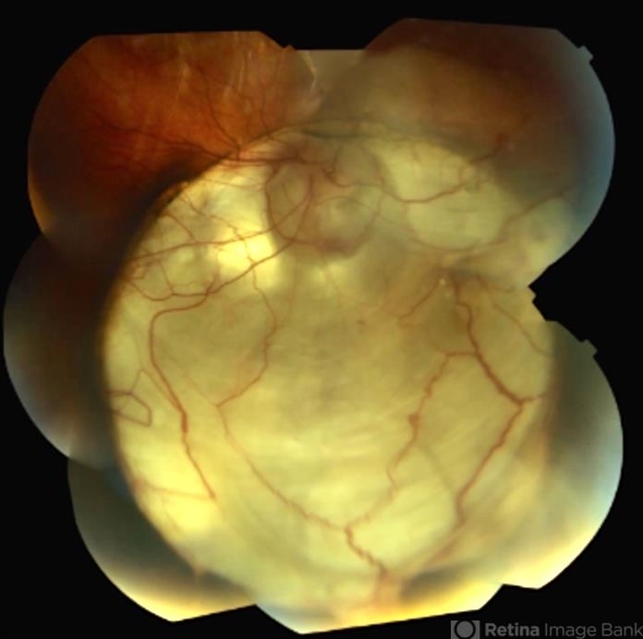

- Optic Nerve Coloboma

- coloboma of optic disc, coloboma of the optic nerve

- This 18-year-old woman has an optic nerve coloboma right eye with longstanding poor vision.